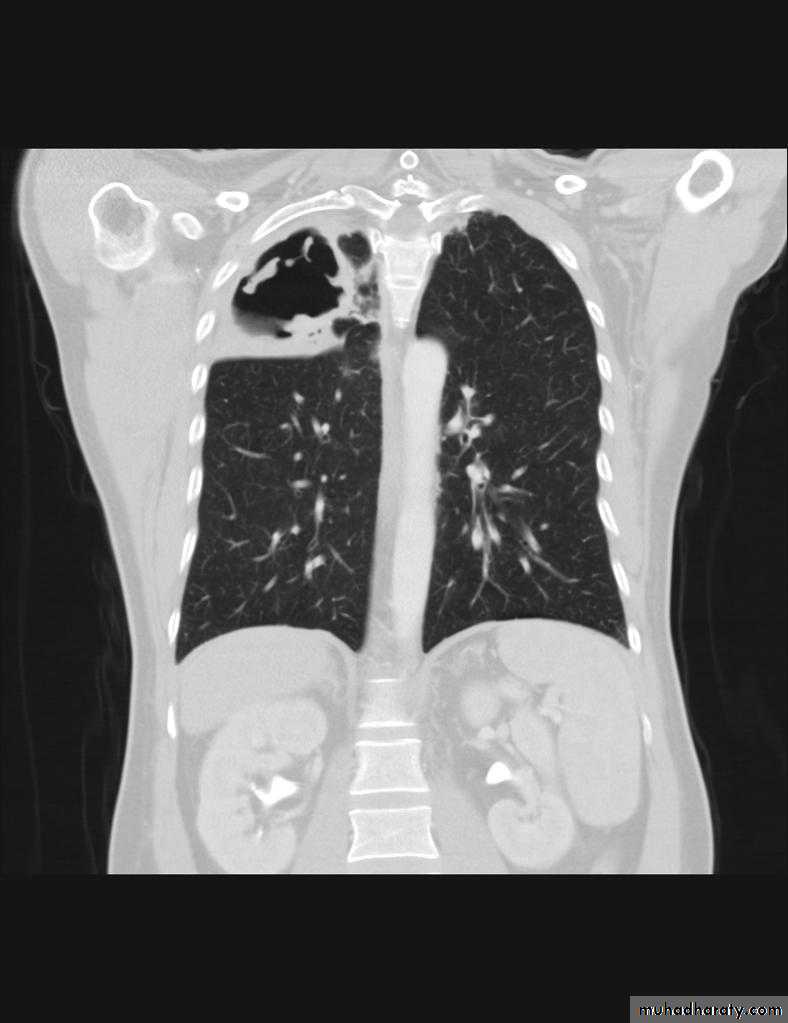

Pulmonary emphysema is defined as the "abnormal permanent enlargement of the airspaces distal to the terminal bronchioles accompanied by destruction of the alveolar wall and without obvious fibrosis". Emphysema is one of the entities grouped together as chronic obstructive pulmonary diseaseRadiographic features

Plain filmExcept in the case of very advanced disease with bulla formation, chest radiography does not image emphysema directly, but rather infers the diagnosis due to associated features :

hyperinflation:

1.flattened hemidiaphragm(s): most reliable sign

2.ncreased and usually irregular radiolucency of the lungs

9.vascular changes paucity of blood vessels ( absent pulmonary markings in outer 1/3 of the lung fields )